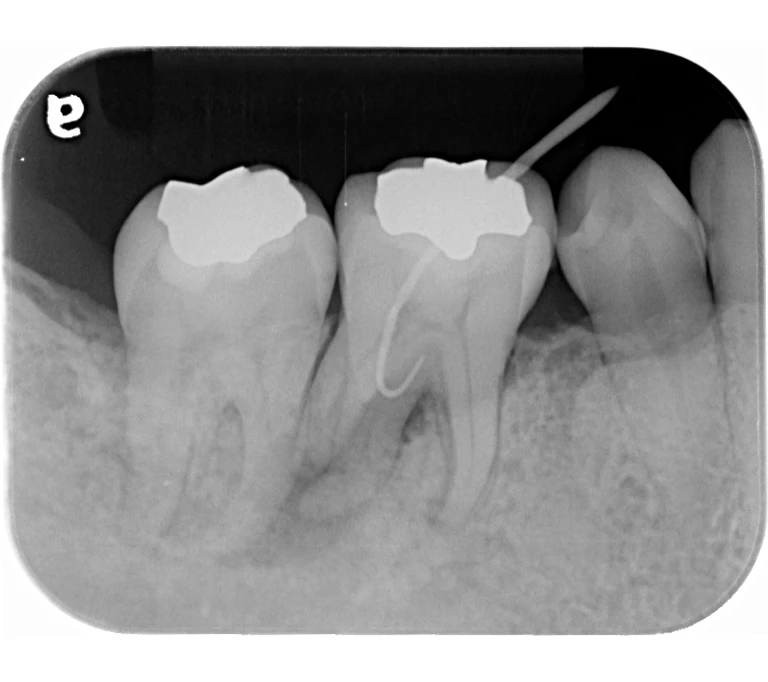

case 3.

治療前

治療後

| 主訴 | 左下奥歯が痛い、歯ぐきの腫れ。 前医で抜歯を提案されたがセカンドオピニオン希望でご来院。 |

|---|---|

| 治療期間 | 約半年(6か月) |

| 治療費 | 約5万円 |

| 治療内容 | 前医ではラバーダム不使用であったため、ラバーダム、マイクロスコープ下にて根管治療を施術。 痛みは消失したが腫れは治らなかったため、意図的再植を行い腫れは消失した。治療後のレントゲンは意図的再植後3年経過したもの。 |

| 治療のリスク | マイクロスコープやCTを使用し、可能な限り精密な根管治療を行っていますが、歯根の形態や病変の大きさ、過去の治療履歴などにより、治癒が得られない場合があります。 また、治療後に再感染や歯根破折が生じることもあり、その場合は再治療や抜歯が必要となることがあります。 治療結果には個人差があり、すべての症例で同様の経過を保証するものではありません。 |